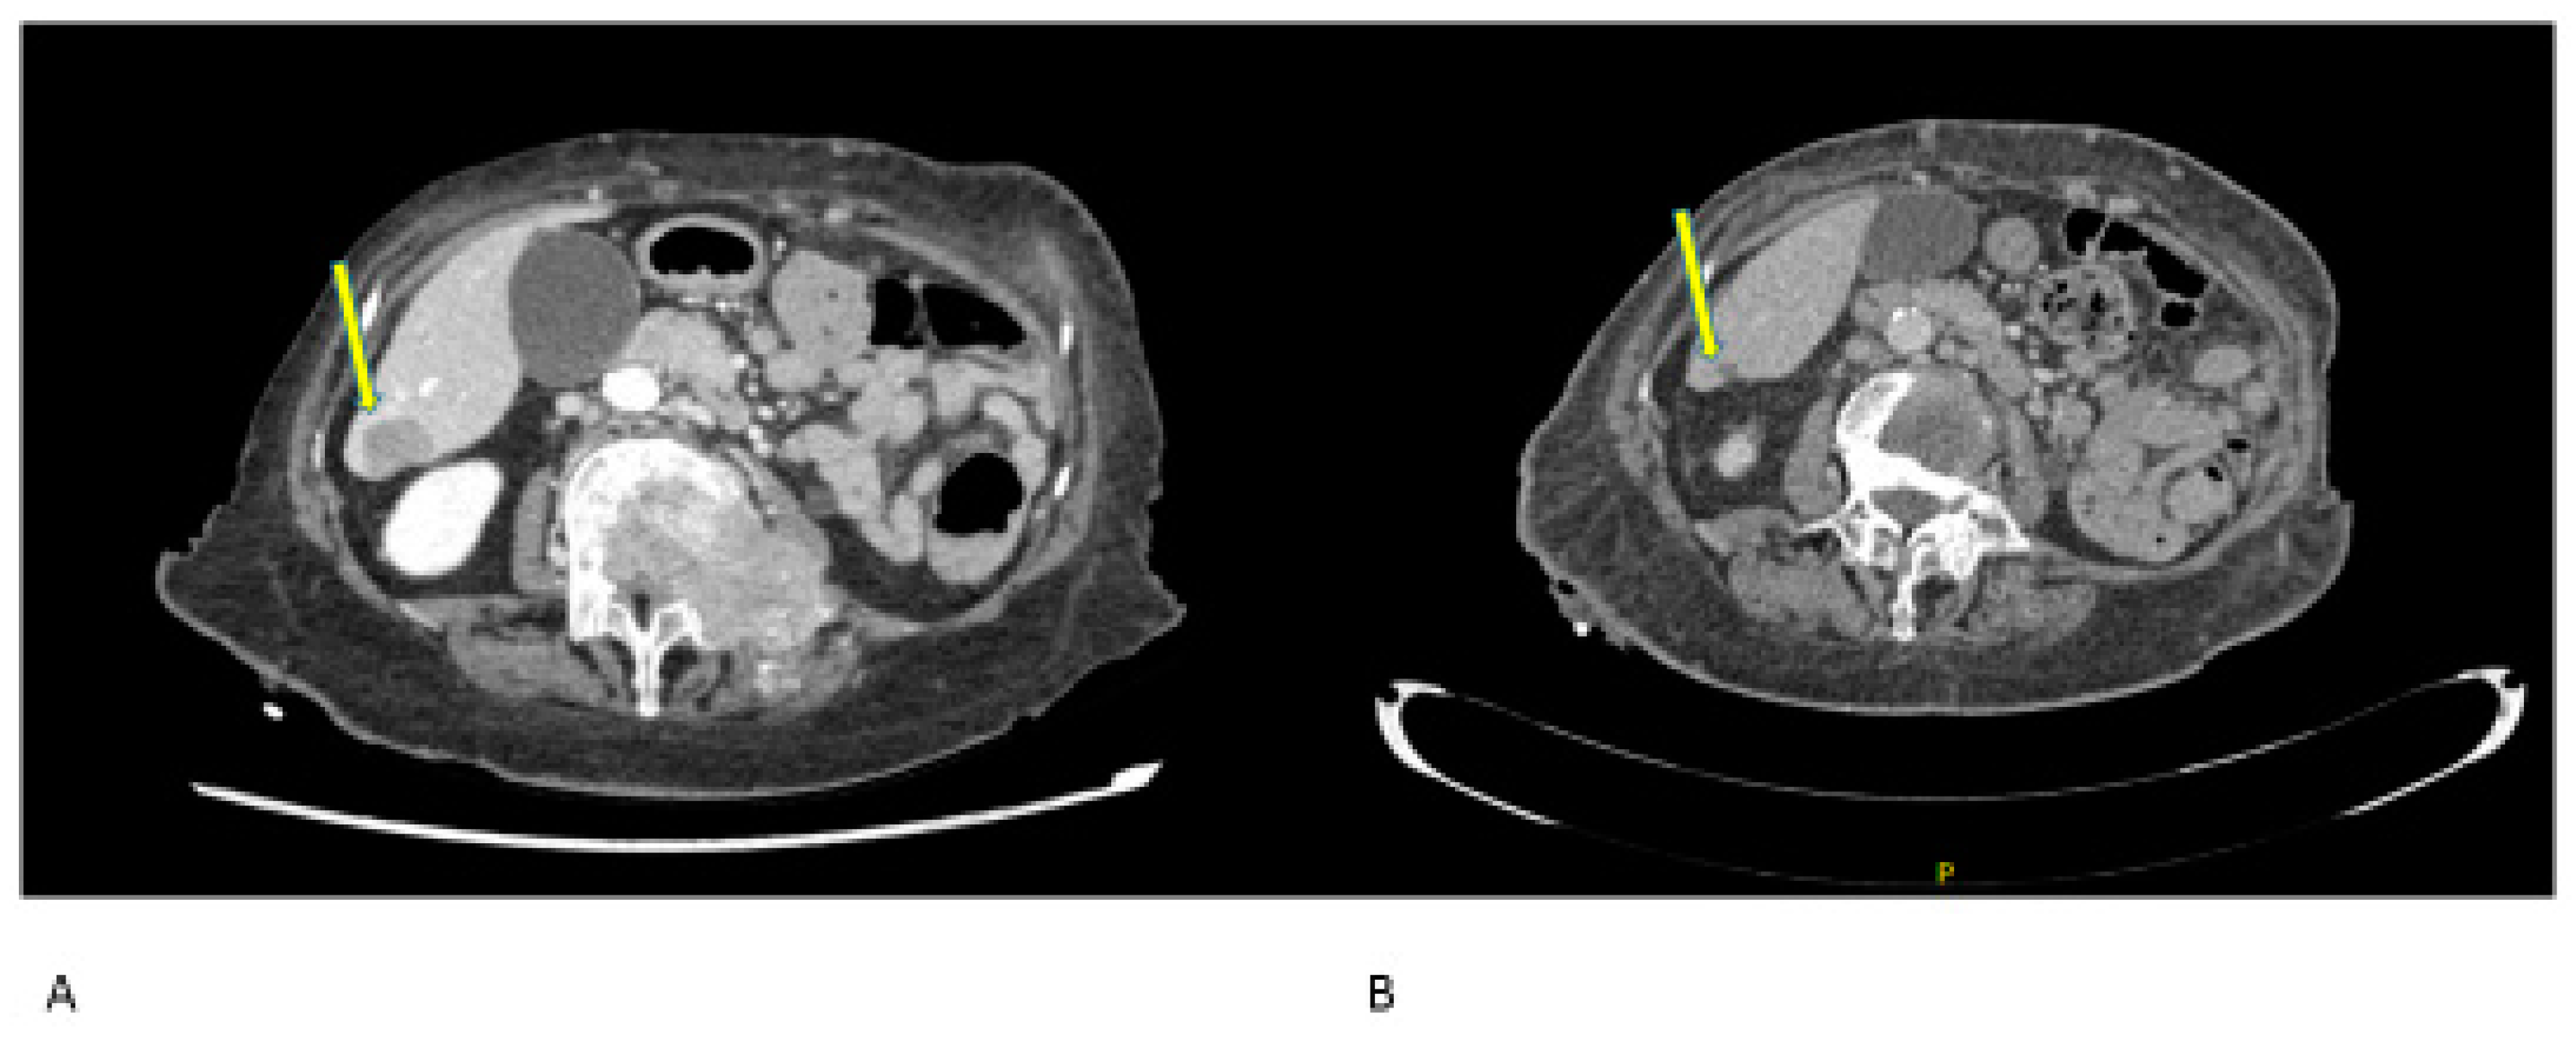

- Case 1:

- Case 2:

- Case 3:

- Case 4:

- Case 5:

- Case 6: